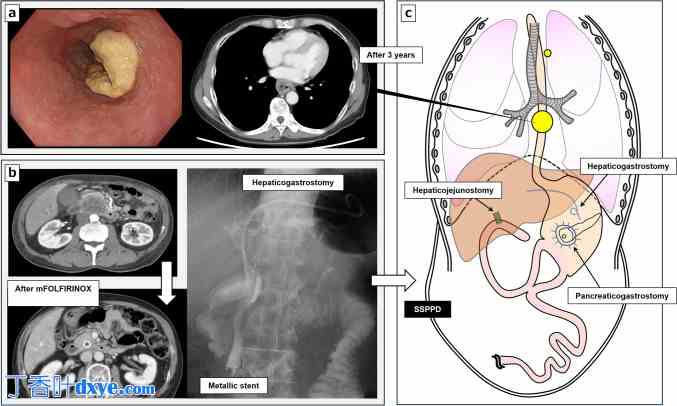

一名 60 岁男性因吞咽困难从外院转诊,诊断为临床 III 期(T3、N1、M0)中段胸段食管鳞状细胞癌(TNM 分期第 8 版)(图 1a)。患者 3 年前在院因晚期胰腺癌行次全保胃腹膜透析 (SSPPD)。患者 57 岁时被诊断为临床 III 期(T4、N0、M0)胰头癌(TNM 分期第 8 版)。患者有严重的梗阻性黄疸,因此保留了胆管金属支架,并首先进行了内镜超声引导下的肝胃吻合术。经过约 7 个月的改良亚叶酸、5-氟尿嘧啶、伊立替康和奥沙利铂 (mFOLFIRINOX) 抗癌药物治疗后,肿瘤缩小并可切除,同时保留了肠系膜上血管(图 1b)。随后,患者接受了 SSPPD 胰胃吻合术作为转换手术,以避免胰瘘和术后出血,确保安全性和长期胰管通畅(图 1c)。手术时间为 10 小时 53 分钟,失血量为 2370 毫升。患者于术后第 22 天出院,无并发症。胰腺癌处于最终 III 期(T3,N0 [0/23],M0,2 级)。术后给予替加氟、吉美嘧啶和奥替拉西 (TS-1) 辅助化疗 6 个月。由于SSPPD术后3年发现的晚期食管癌的标准治疗是术前化疗,作者首先选择了新辅助化疗(DCF方案:多西他赛35 mg/m2,顺铂40 mg/m2,氟尿嘧啶400 mg/m2)。经过两个疗程的新辅助化疗后,根据《实体肿瘤标准》1.1版中的疗效评估标准,确定食管癌部分缓解(肿瘤缩小61%)(图2a)。

图1.

十二指肠切除术及食管癌示意图。a. 中段胸段食管鳞状细胞癌T3N1M0。 b 胰头癌 T4N0M0 患者接受 mFOLFIRINOX 化疗前后胆管金属支架置入及肝胃吻合术。c 食管癌治疗开始前胰十二指肠切除术及胰胃吻合术后重建示意图。SSPPD 保胃次全胰十二指肠切除术